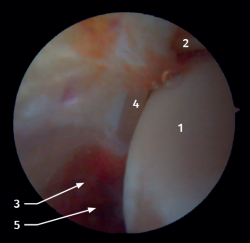

Anterior arthroscopic view

Twenty percent of the ATFL is intra-articular(7). On adopting an anteromedial access of the ankle, directing the arthroscope laterally, we can see the distal fibers of the ATFL with their oblique distribution and their continuation with the anterior talofibular ligament (Figure 2). If we move into the tibiotalar joint, we see the distal tibiofibular joint with the syndesmotic recess occupied by synovial tissue (Figure 3).

Figure 2. Anterolateral arthroscopic view of the right ankle. 1: talar dome; 2: anterior aspect of the tibia; 3: fibula; 4: distal fibers of the anterior tibiofibular ligament; 5: anterior talofibular ligament.

Figure 3. Anterolateral arthroscopic view of a right ankle on entering the tibiotalar zone. 1: talar dome; 2: articular aspect of the tibia; 3: fibula; 4: distal tibiofibular joint; 5: distal fibers of the anterior tibiofibular ligament.